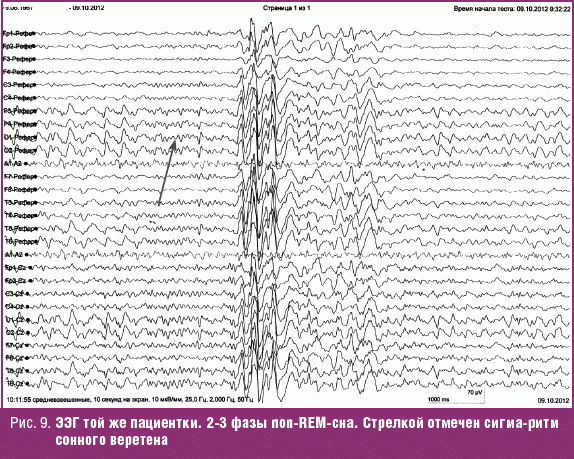

Ээг быстрого сна